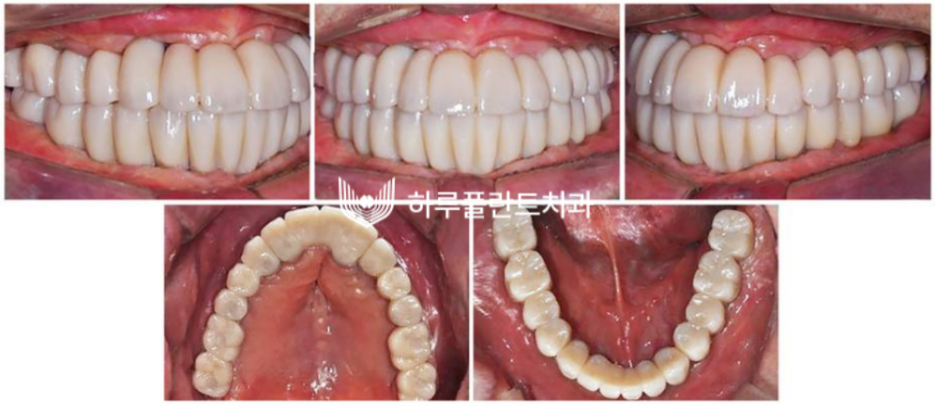

임플란트 완성 후 구강 내 사진입니다.

아주 튼튼하게 식립되었고

환자분도 매우 만족한 사례입니다.

난이도 높은 전악임플란트가

성공적으로 마무리 된 후 의 구강 사진입니다.

치아의 기능은 물론 심미성까지

완벽히 회복된 모습이죠.